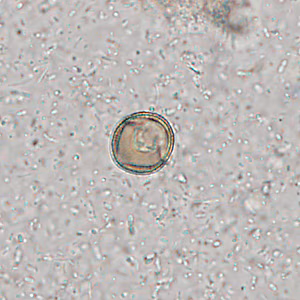

Case #309 – October, 2011

A 19-year-old male presented to his health care provider with moderate abdominal cramping and intermittent diarrhea that started approximately one week following a camping trip in the southeastern United States. A fecal specimen in 10% formalin was submitted for ova-and-parasite (O&P) examination. A formalin-ethyl acetate (FEA) concentrate was performed and Figures A and B show what was observed at 400x magnification in a wet mount preparation. The objects measured 17-20 micrometers on average. What is your diagnosis? Based on what criteria?

Figure B